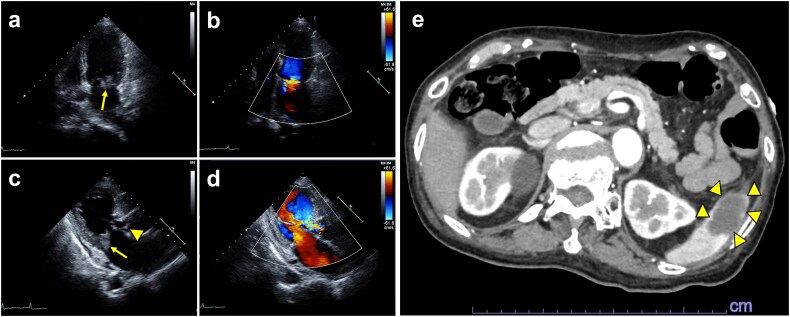

感染性心内膜炎(IE)是一种危及生命的疾病,通常需要手术干预;然而,在手术禁忌的情况下,保守治疗依赖于适当的抗生素治疗。此外,抗生素的修改可能是关键,因为某些药物在解决感染和相关并发症方面可能更优越。我们提出的情况下,一个88岁的妇女与IE由于血管链球菌,成功地治疗口服抗生素。经胸超声心动图显示二尖瓣和主动脉瓣赘生物,伴有中度至重度瓣膜功能障碍。尽管静脉注射氨苄西林6周,她的病情改善有限。策略性地改用左氧氟沙星导致了显著的临床进展,显著减少了植被大小和正常的炎症标志物。左氧氟沙星的有效性,由于其生物膜渗透和杀菌活性,表明定制抗生素方案有可能取得积极的结果。这个病例说明,即使标准治疗不成功,仔细的抗生素调整也会显著影响治疗过程。

Infective endocarditis (IE) is a life-threatening condition, often requiring surgical intervention; however, in cases where surgery is contraindicated, conservative management relies on appropriate antibiotic therapy. Moreover, modification of antibiotics can be critical, as certain agents may be superior in resolving infection and associated complications. We present the case of an 88-year-old woman with IE due to Streptococcus anginosus, successfully treated with oral antibiotics. Transthoracic echocardiography revealed vegetations on the mitral and aortic valves, along with moderate-to-severe valvular dysfunction. Despite 6-week treatment with intravenous ampicillin, her condition showed limited improvement. A strategic switch to levofloxacin led to remarkable clinical progress, with significantly reduced vegetation size and normalized inflammatory markers. The effectiveness of levofloxacin, due to its biofilm penetration and bactericidal activity, indicates the potential for customized antibiotic regimens to achieve positive outcomes. This case illustrates that even when standard treatment is unsuccessful, careful antibiotic adjustment can significantly impact the therapeutic course.